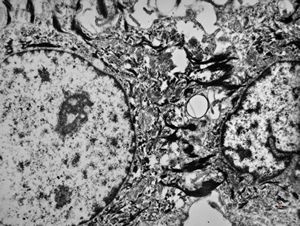

F,41y. | synovial metaplasia - capsule of implantate

F,41y. | synovial metaplasia - capsule of implantate

F,41y. | synovial metaplasia - capsule of implantate

F,41y. | synovial metaplasia - capsule of implantate

F,41y. | synovial metaplasia - capsule of implantate

F,41y. | synovial metaplasia - capsule of implantate

F,41y. | synovial metaplasia - capsule of implantate

F,41y. | synovial metaplasia - capsule of implantate

F,41y. | synovial metaplasia - capsule of implantate